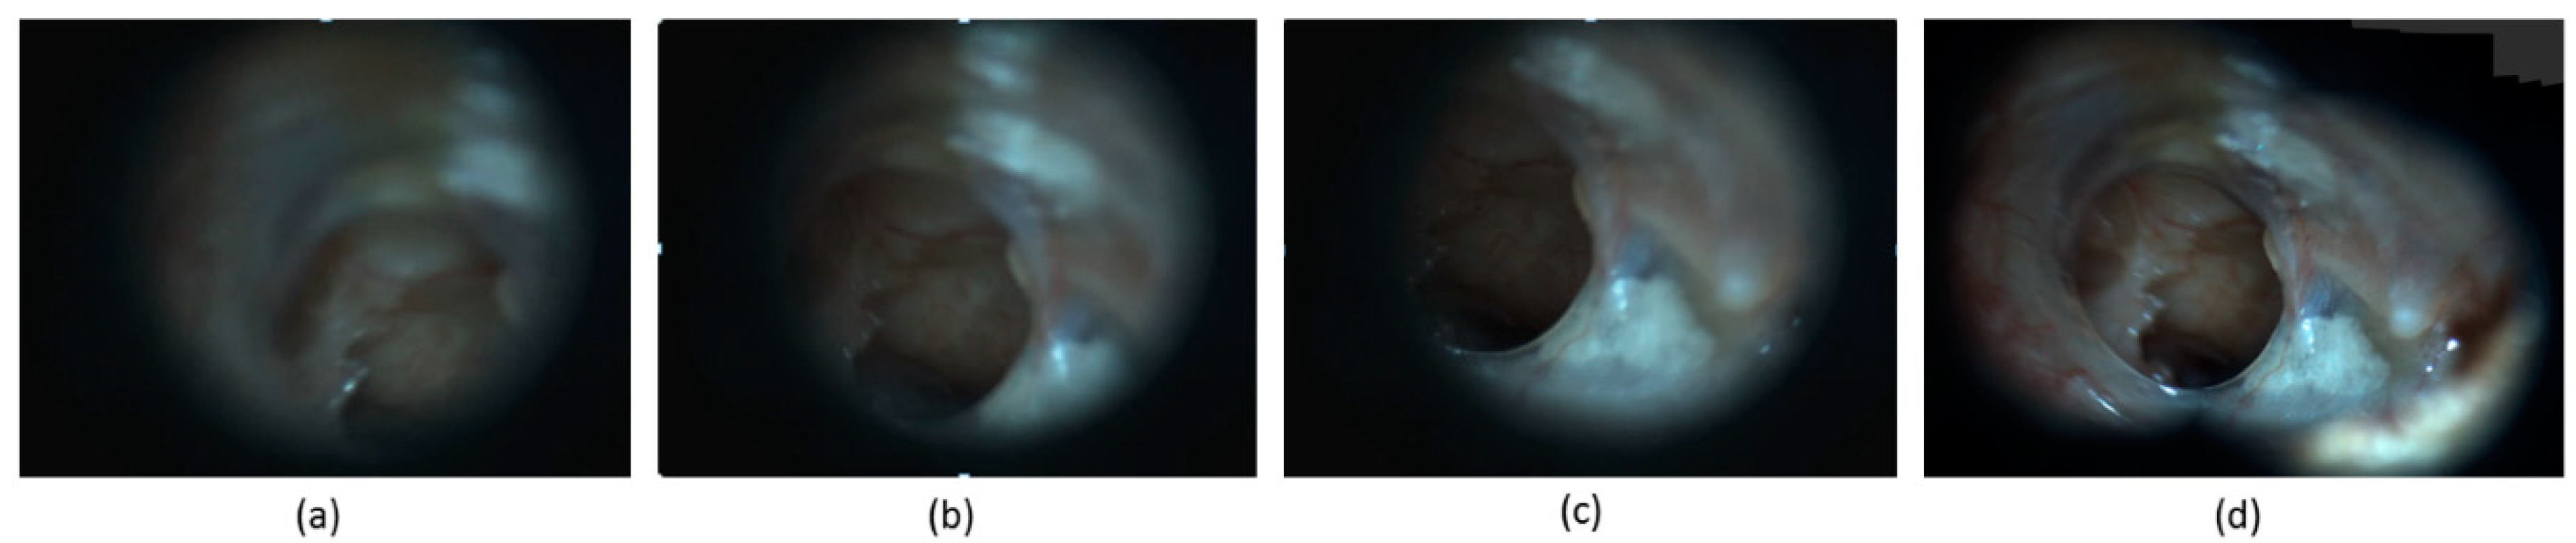

Figure 5 demonstrates the image stitching process for the three of selected frames. In this example, the image stitching helped to obtain a single image that contains a more comprehensive view of the pathology.

Figure 5. The image stitching result for three of the selected frames. The stitching process expands the original field-of-view of the input frames. (ac) Input images, (d) stitching result.